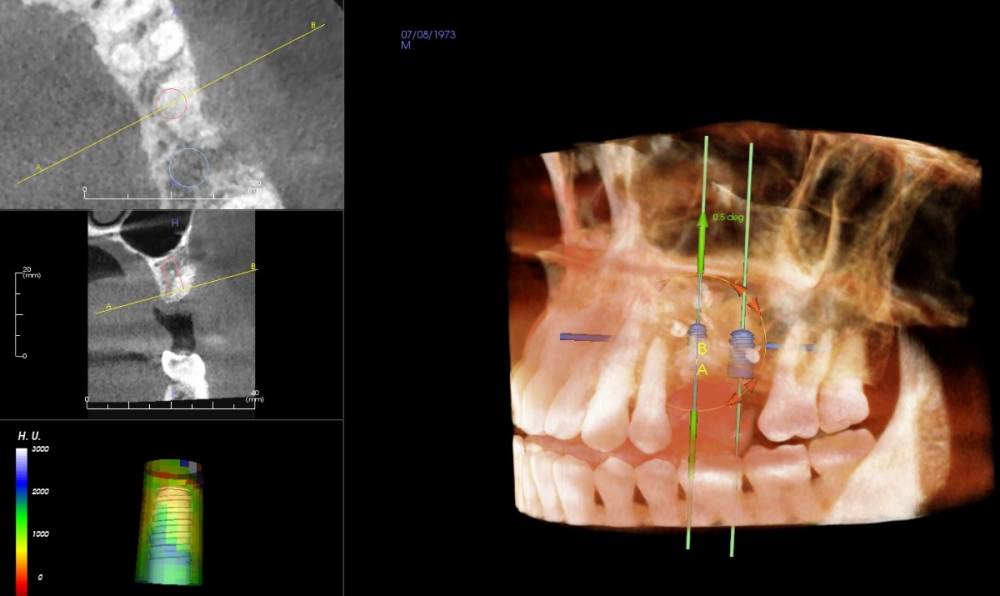

Smut Опубликовано 24 ноября, 2021 Автор Поделиться Опубликовано 24 ноября, 2021 https://drive.google.com/drive/folders/11eojiqr5oxV2DyflrsOpWAdLUCzuzkTC?usp=sharing Ссылка на комментарий

Irouil Опубликовано 24 ноября, 2021 Поделиться Опубликовано 24 ноября, 2021 В области отсутствующего 5-го зуба Вам ранее проводилась костная пластика, оценка состояния тканей после ее проведения должна происходить уже при раскрытии раны, но на снимке все выглядит хорошо. Как давно Вам проводили эту операцию? В области отсутствующего 6-го зуба действительно потребуется синус-лифт, при латеральном доступе («открытом» варианте операции) действительно нужно создать дополнительное окно, но не все хирурги укрывают это окно мембраной и данная операция не преследует цель восстановления костной стенки в области данного окна - так как синус лифт чаще всего проводится по верхней край окна, то костная ткань чаще всего вырастает внутри пазухи практически «заподлицо» со сформированными краями и никаких значимых последствий наличие подобного окна не имеет при определённом навыке в Вашем случае вполне возможно провести синус лифт крестальным доступом, то есть прямо через дырку, просверленную для импланта 1 1 Ссылка на комментарий